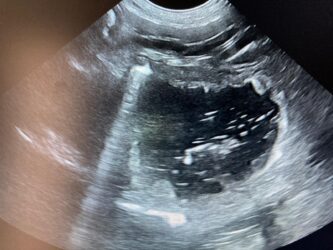

Dimitri, CV, 9.6kg, 11j, MC, bijgeruis 4/6 waarvoor hij vetmedin krijgt en opgevolgd wordt door cardioloog:

21/08/2025: Bij buurtcollega aangeboden voor hematurie. Plast vlot, op’t einde bloed te zien. Mevr. kookt zelf voor hem. Echo gehad + UOZ (geen idee hoe dit werd gecollecteerd) gedaan. Veel bloed in de…